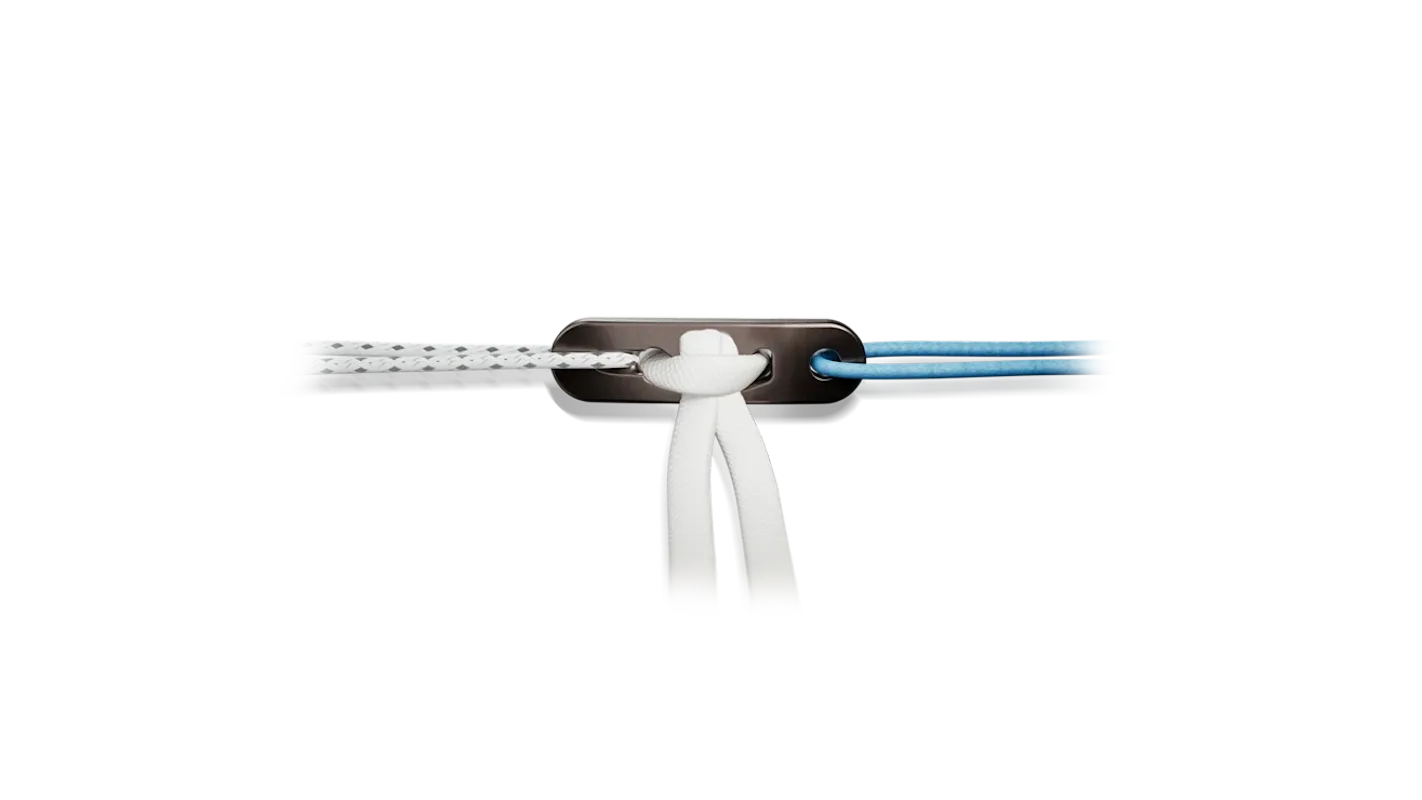

Arthrex es líder global en soluciones para artroscopía y medicina deportiva, ofreciendo implantes, suturas e instrumentación desarrollados para lograr reparaciones más fuertes, reconstrucciones anatómicas y una recuperación más rápida del paciente. Nuestro portafolio cubre hombro, rodilla, tobillo y muñeca, con tecnología de última generación para cada procedimiento.

- Implantes para reconstrucción de LCA/LCP

- Consumibles

- Instrumental